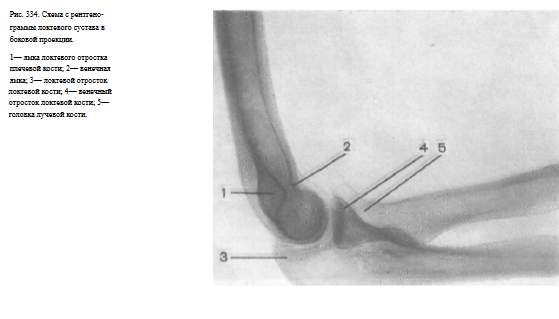

Информативность снимка. На снимке определяются дистальный отдел плечевой кости и проксимальные отделы костей предплечья. Хорошо видны локтевой и венечный отростки локтевой кости, головка и шейка лучевой кости.

Блок и головка плечевой кости проекционно наслаиваются друг на друга и определяются на снимке в виде концентрических кругов, что и служит показателем правильности укладки (рис. 334).